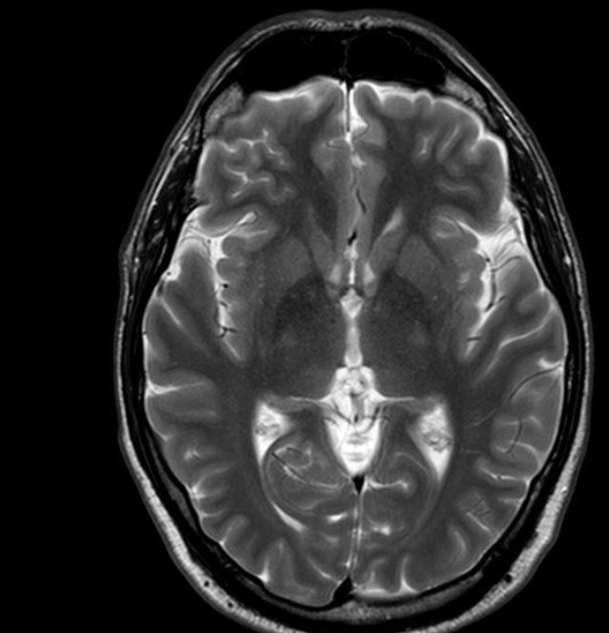

뇌 쪽 검사도 목적에 따라 달라요. 뇌출혈이나 외상이 의심되면 빠르게 판단 가능한 CT가 먼저 쓰입니다. 실제로 제 지인은 갑자기 두통과 어지러움이 심해져서 응급실에 갔는데, CT로 바로 뇌출혈 여부를 확인했어요. 이후 좀 더 정밀한 확인이 필요해 MRI도 찍었는데, 작은 병변까지는 MRI가 훨씬 잘 보여준다고 하더라고요. X-ray는 뇌 자체보다는 두개골 상태를 볼 때 사용돼요.

병원에 가면 MRI나 CT 찍자고 하는 경우가 종종 있어요. 겉보기엔 비슷해 보여도 이 둘은 검사 방식부터 목적까지 완전히 다릅니다. 제 친구는 얼마 전 무릎 통증으로 병원을 갔는데, 의사 선생님이 X-ray 먼저 찍고 나중에 MRI를 추가로 권하더라고요. 알고 보니 뼈 상태는 괜찮은데 인대 손상이 의심돼서 MRI로 확인해야 했대요. 이렇게 MRI는 자기장과 전파를 이용해 근육, 인대, 뇌처럼 부드러운 조직을 자세히 살펴볼 수 있고, CT는 X선을 여러 방향에서 쏴서 컴퓨터로 이미지를 만들어내기 때문에 응급상황에서 빠른 진단에 유리해요.